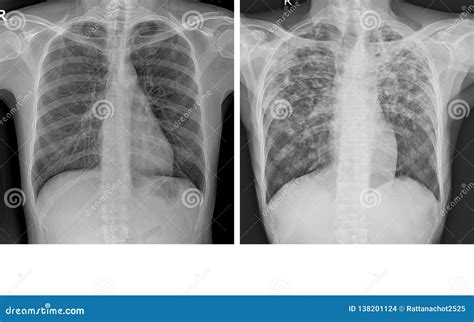

Common Abnormalities in Lung X-rays

While a normal lung X-ray shows no signs of disease, it is essential to recognize common abnormalities that may appear on a lung X-ray. These include:

• Pneumonia: Inflammation of the lung tissue, often caused by infection, which appears as opacities or infiltrates.

• Lung Cancer: Tumors or nodules that may appear as masses or opacities.

• Pleural Effusion: Fluid accumulation around the lungs, which appears as a white area at the lung bases.

• Pneumothorax: Air in the pleural space, which appears as a black area without lung markings.

• Tuberculosis: Infections that can cause cavitary lesions or nodules.

These abnormalities can significantly impact a patient's health and require prompt diagnosis and treatment.